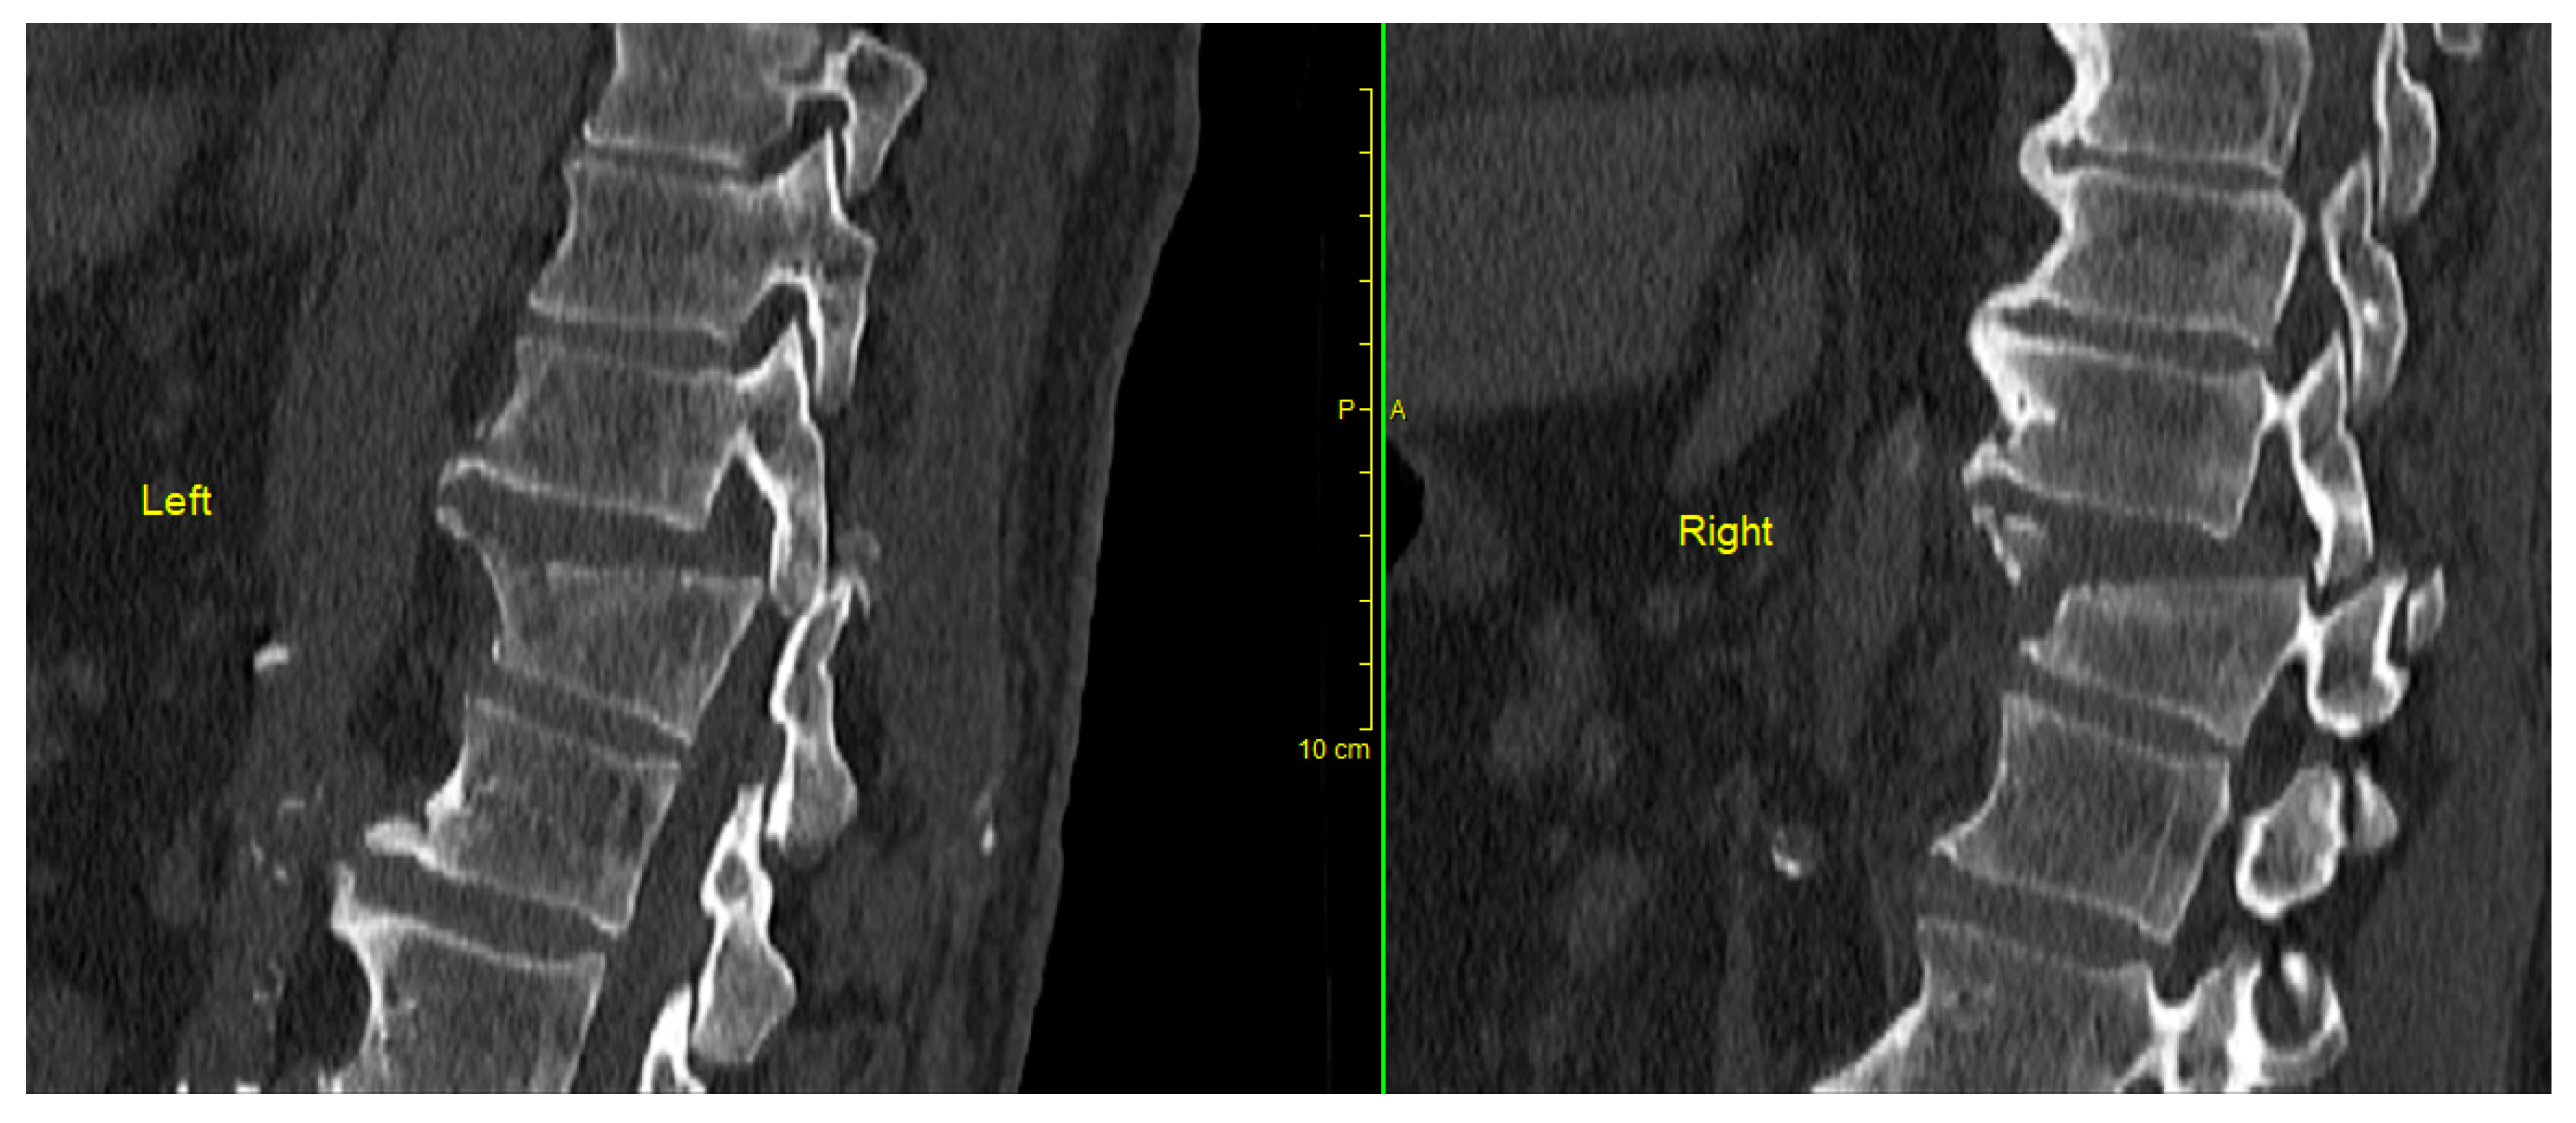

Figure 7. Computerized Tomography scan of thoracic fracture dislocation (Th9/Th10) successfully and safely reduced using the described technique.